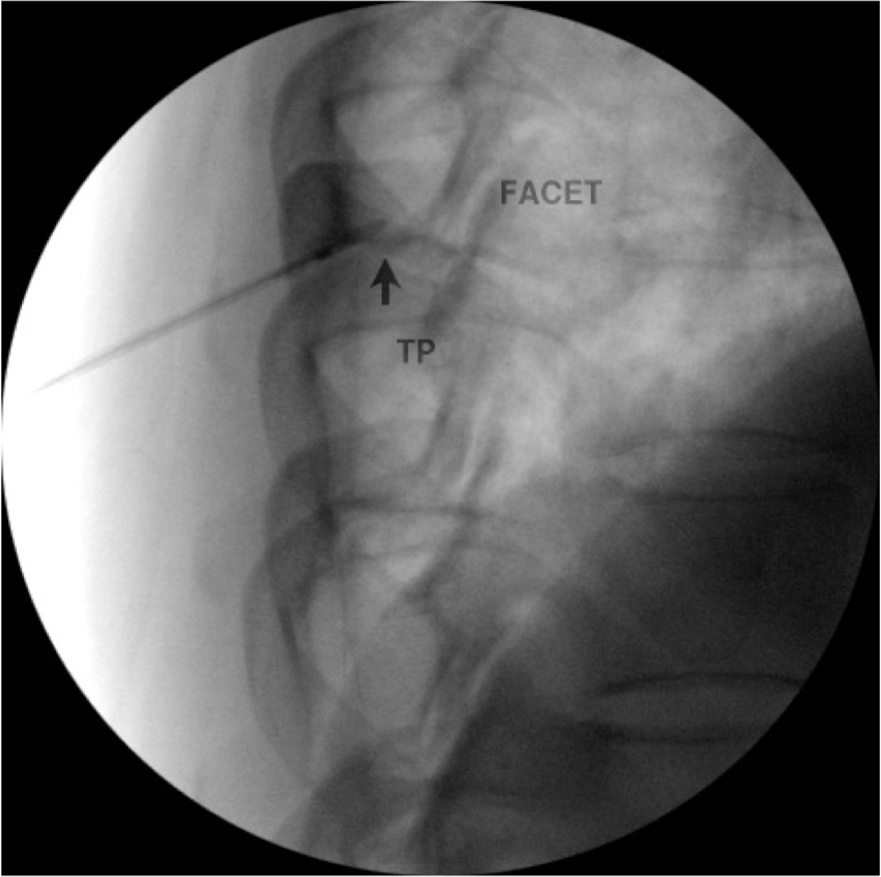

Diagnostic blocks in the thoracic region are performed by placing the needle at the superior lateral corner of the transverse process where the medial branch transverses via a posterior approach. These targets are especially true for medial branches T1-4 and T9-T10. (Figure 13). A separate injection can be made at each level. A small amount of local anesthetic (0.5 ml of 0.5% bupivacaine or 2% lidocaine) should be injected at each level. It is important to keep the needle over bone at all times to avoid damage to the pleura. It is also important to note that there is greater variability at the levels of the T5-T8. At these levels the medial branches are often found in the intertransverse spaces rather than on bone. This fact can lead to difficult when performing the procedure at these levels.

Figure 18c. Thoracic medial branch denervation procedure. The RF probe has been inserted into the RF needle and is in position just off the superior lateral edge of the T6 transverse process.

Figure 18d. Thoracic medial branch denervation procedure. Lateral view of probe in position posterior to the foramen.